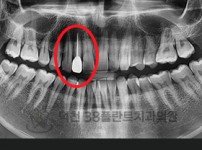

치료전후